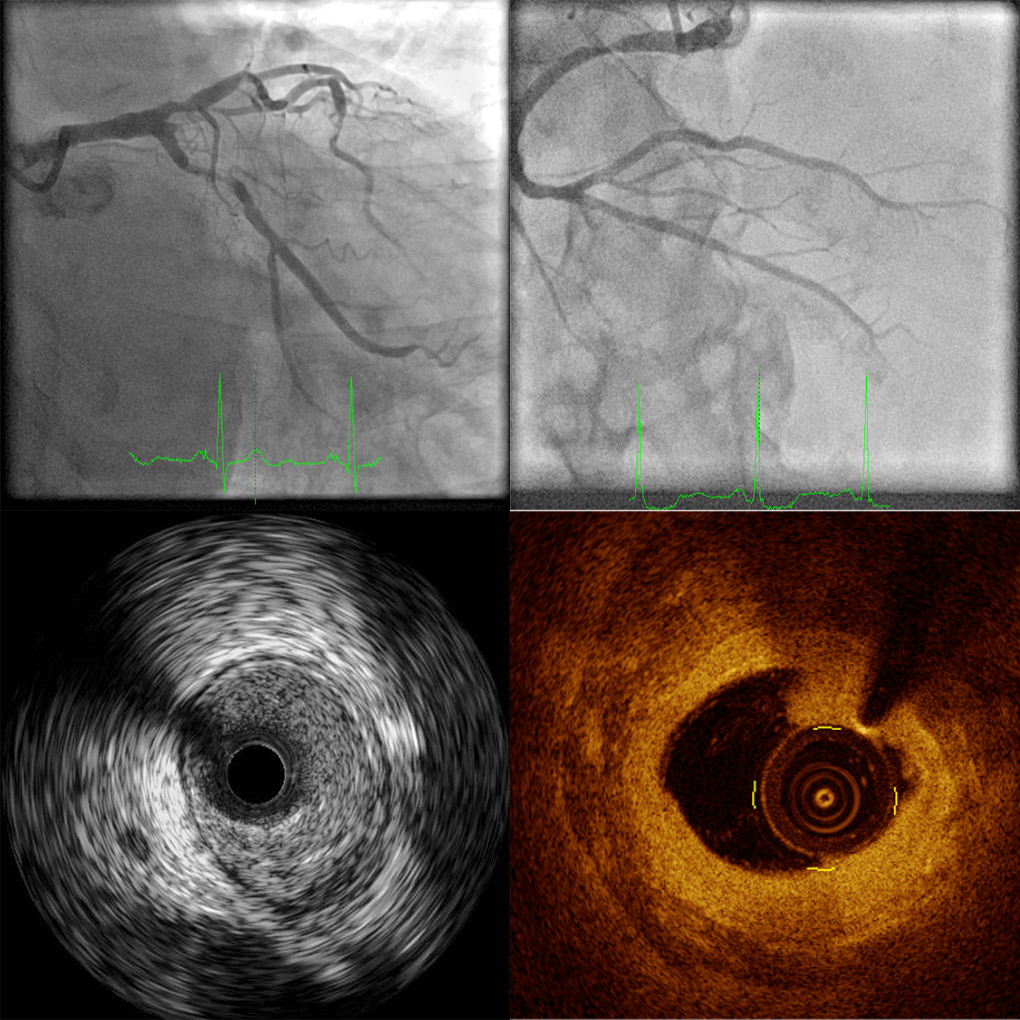

We analyze both quantitative and qualitative your IVUS, OCT and angiograms for your  research projects using licensed dedicated software.

We can provide clinical interpretation reports and measurements of your IVUS and OCT acquisitions. (like a radiology report of an X-ray picture).